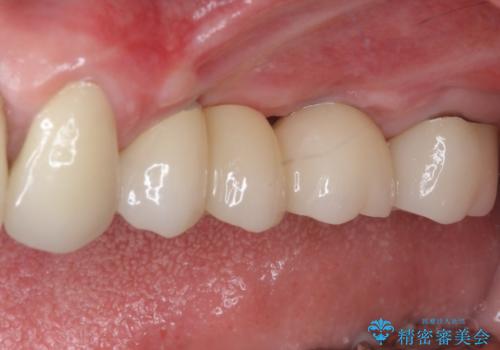

変色した前歯をオールセラミッククラウンに

診察やレントゲン写真より神経組織の失活が認められたため、根管治療、ファイバーコアによる土台築製後、オールセラミッククラウンにて補綴することとしました。

神経を取り除いた歯は時間とともに変色してきます。

クリーニングやホワイトニングでは改善できないため、オールセラミッククラウンなどによる補綴治療が必要となります。